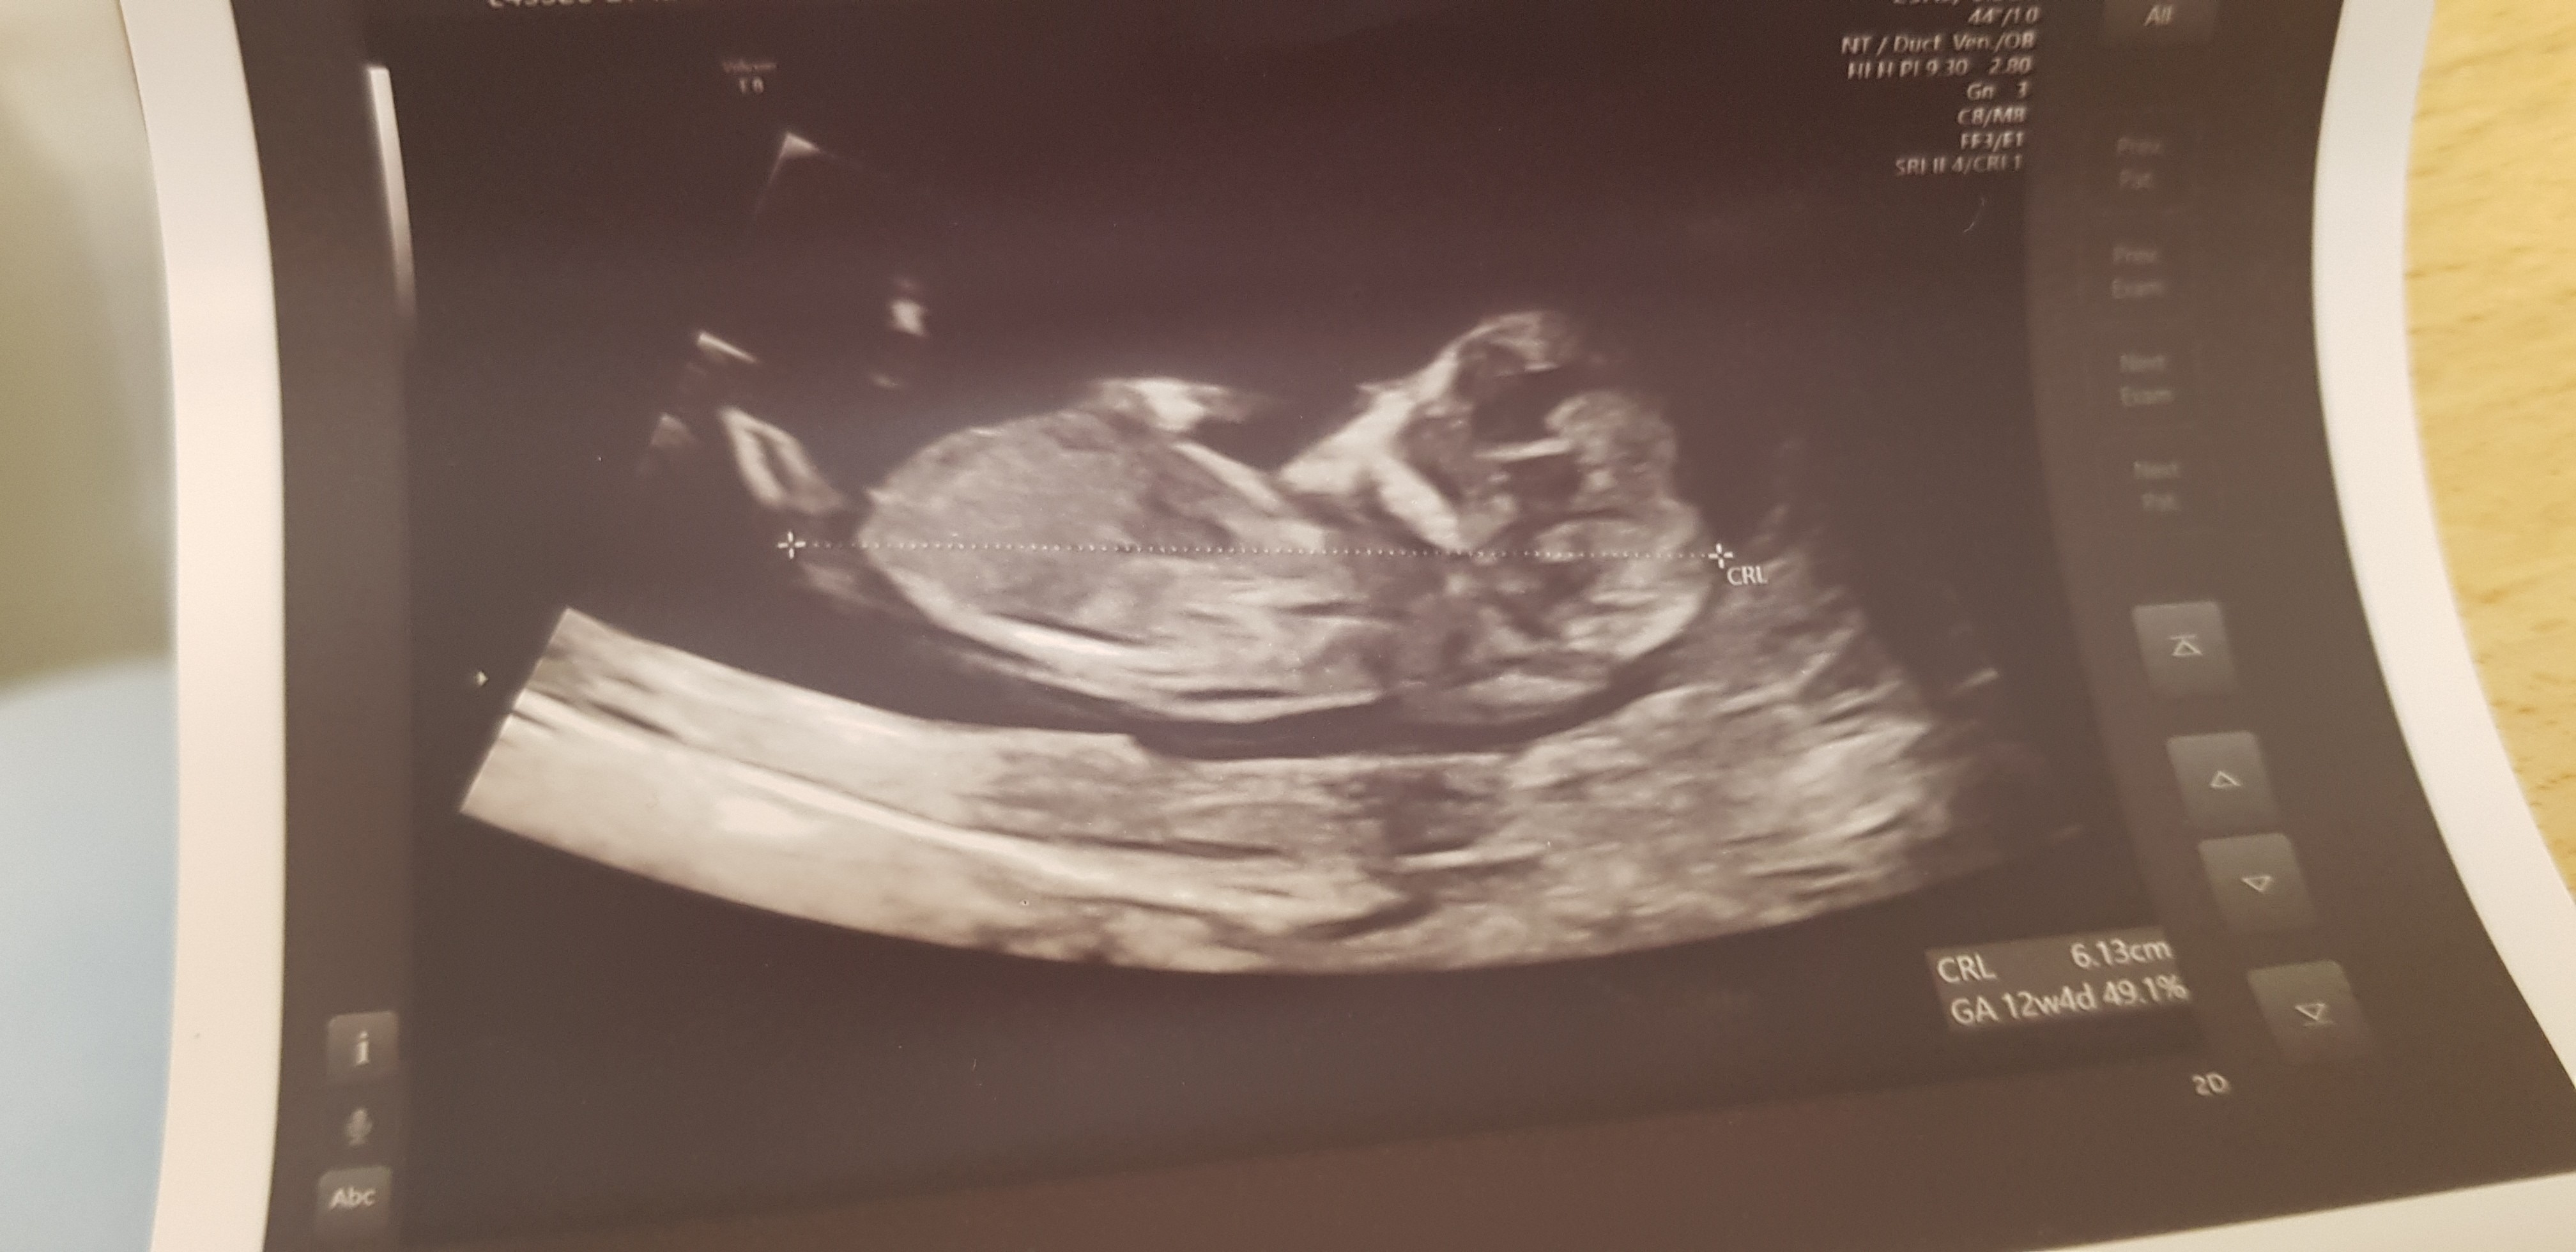

Witajcie e-ciocie! Jestem malym, jak na razie zdrowym 6-cemtymetrowym człowiekiem 🥰

• 20211208_120433.jpg

886,3 KB · Wyświetleń: 110

Cześć cioteczki ☺️ Mój bobas rośnie jak szalony! Dzisiaj 11+4 z OM, a z USG już 12+1 😱 Aż zaczęłam się martwić, czy przypadkiem na prenatalne nie będzie za duży 😂

Rośnie nam mały leniwiec, bo sobie tak spokojnie leżał i lekarz musiał mi w brzuch popukać, żeby się trochę poruszał :P Wstępnie sprawdził też przezierność karkową i powiedział, że wszystko ok :)